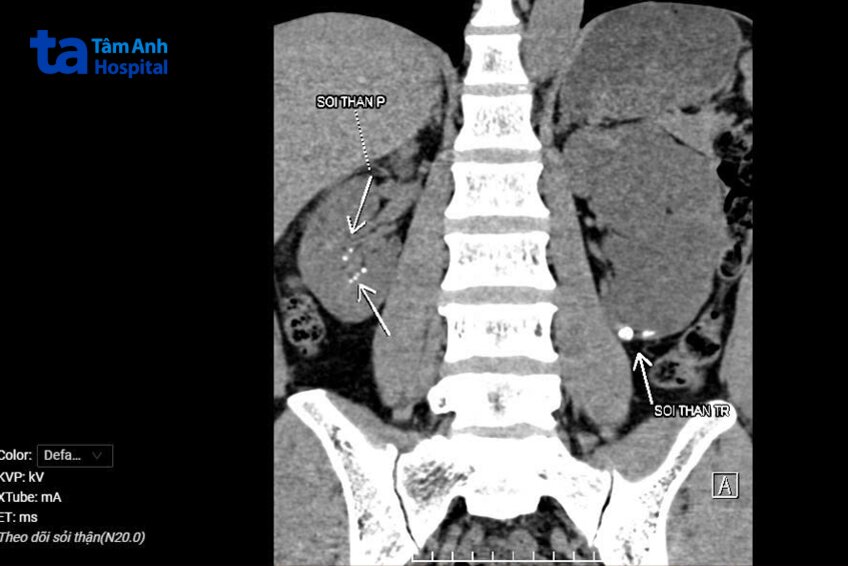

Kết quả chụp cắt lớp vi tính hệ tiết niệu cho thấy thận trái của người bệnh ứ nước nặng, nhu mô thận mỏng, chức năng bài xuất giảm. Ở đoạn niệu quản trái bắt chéo động mạch chậu có viên sỏi kích thước khoảng 5×6 mm, kèm theo nghi ngờ có hẹp niệu quản phía dưới sỏi. Ngoài ra, ở đài dưới thận trái cũng có vài viên sỏi nhỏ, ở thận phải, kích thước nhu mô bình thường, chức năng thận còn bảo tồn, đài bể thận không giãn, rải rác các đài thận có các viên sỏi nhỏ.